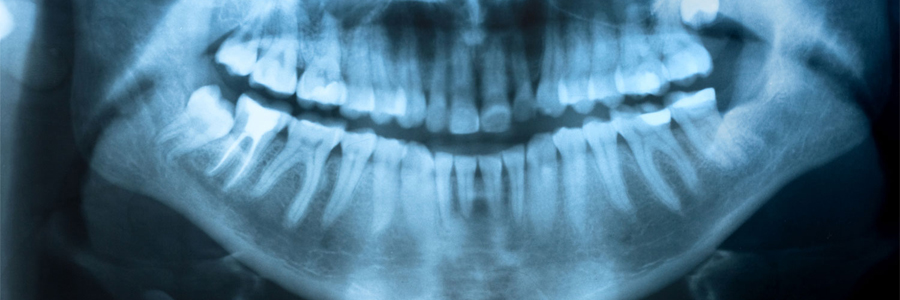

Digital X-Ray

Orthopantogram and cephalogram is a type of dental x-rays. An OPG gives wide views of the lower and upper jaws while a cephalogram is an x-ray of facial structures. A horizontal cephalogram gives a side profile picture of the face, jaws, and delicate tissue to evaluate the connection of the teeth to the jaws, the jaws to skull, and the connection of the delicate tissues to the teeth and jaws. A focused x-ray machine is used to generate the scans. At the time an OPG test, a part of the machine will turn around the patient’s head while they stay in one position either standing or sitting position. The Cephalogram is an x-ray which produces the side views of the face with very precise positioning and to determine the current and future connection of the upper and lower jaws.